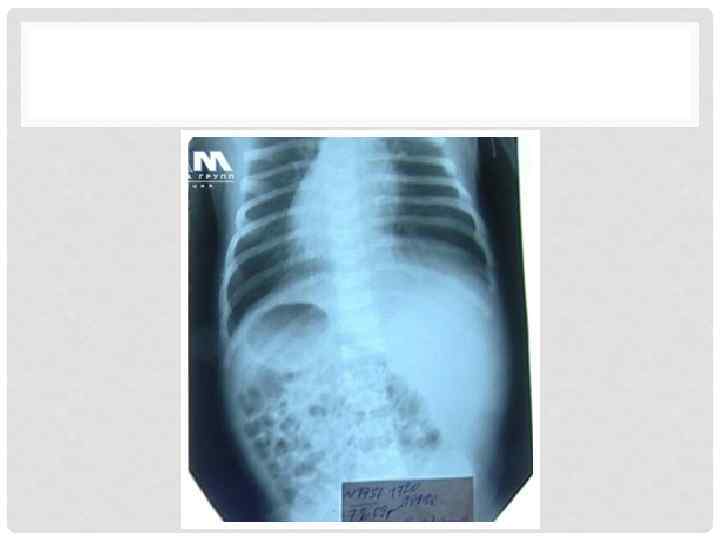

ЭТАПЫ РАЗВИТИЯ БРЮШИНЫ. 4 ЭТАП 12 недель • Усиленный рост кишечной трубки в длину – образование петли: • Нисходящее колено (17 а) • Восходящее колено (17 б) с утолщением – слепой кишкой

ЭТАПЫ РАЗВИТИЯ БРЮШИНЫ. 4 ЭТАП • Восходящее колено (17 б) – поднятие и поворот, перекрывает нисходящее колено и прикрывает 12 П кишку • Слепая кишка под печенью • Ободочная кишка поперек • Редуцируется желточно кишечный проток и часть дорсальной брыжейки в области 12 П и нисходящей ободочной кишок

ЭТАПЫ РАЗВИТИЯ БРЮШИНЫ. 5 ЭТАП После 16 недель • Усиленный рост будущей тонкой кишки • Опускание слепой кишки с формированием восходящей ободочной кишки. • Рост восходящего колена в области сигмовидной кишки

ЭТАПЫ РАЗВИТИЯ БРЮШИНЫ 4 недели 16 недель